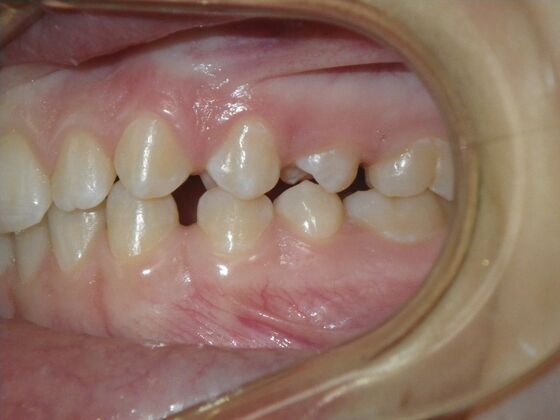

Patient presents desiring all spaces on upper and lower teeth closed. She will need slight expansion of upper arch due to lower molars leaning inward toward tongue. Used nitanium palatal expander with built in rotation of upper molars and lower lip bumper to upright lower first molars. Patient was also informed that her upper lateral incisors would require bonding due to their small size to close all space.